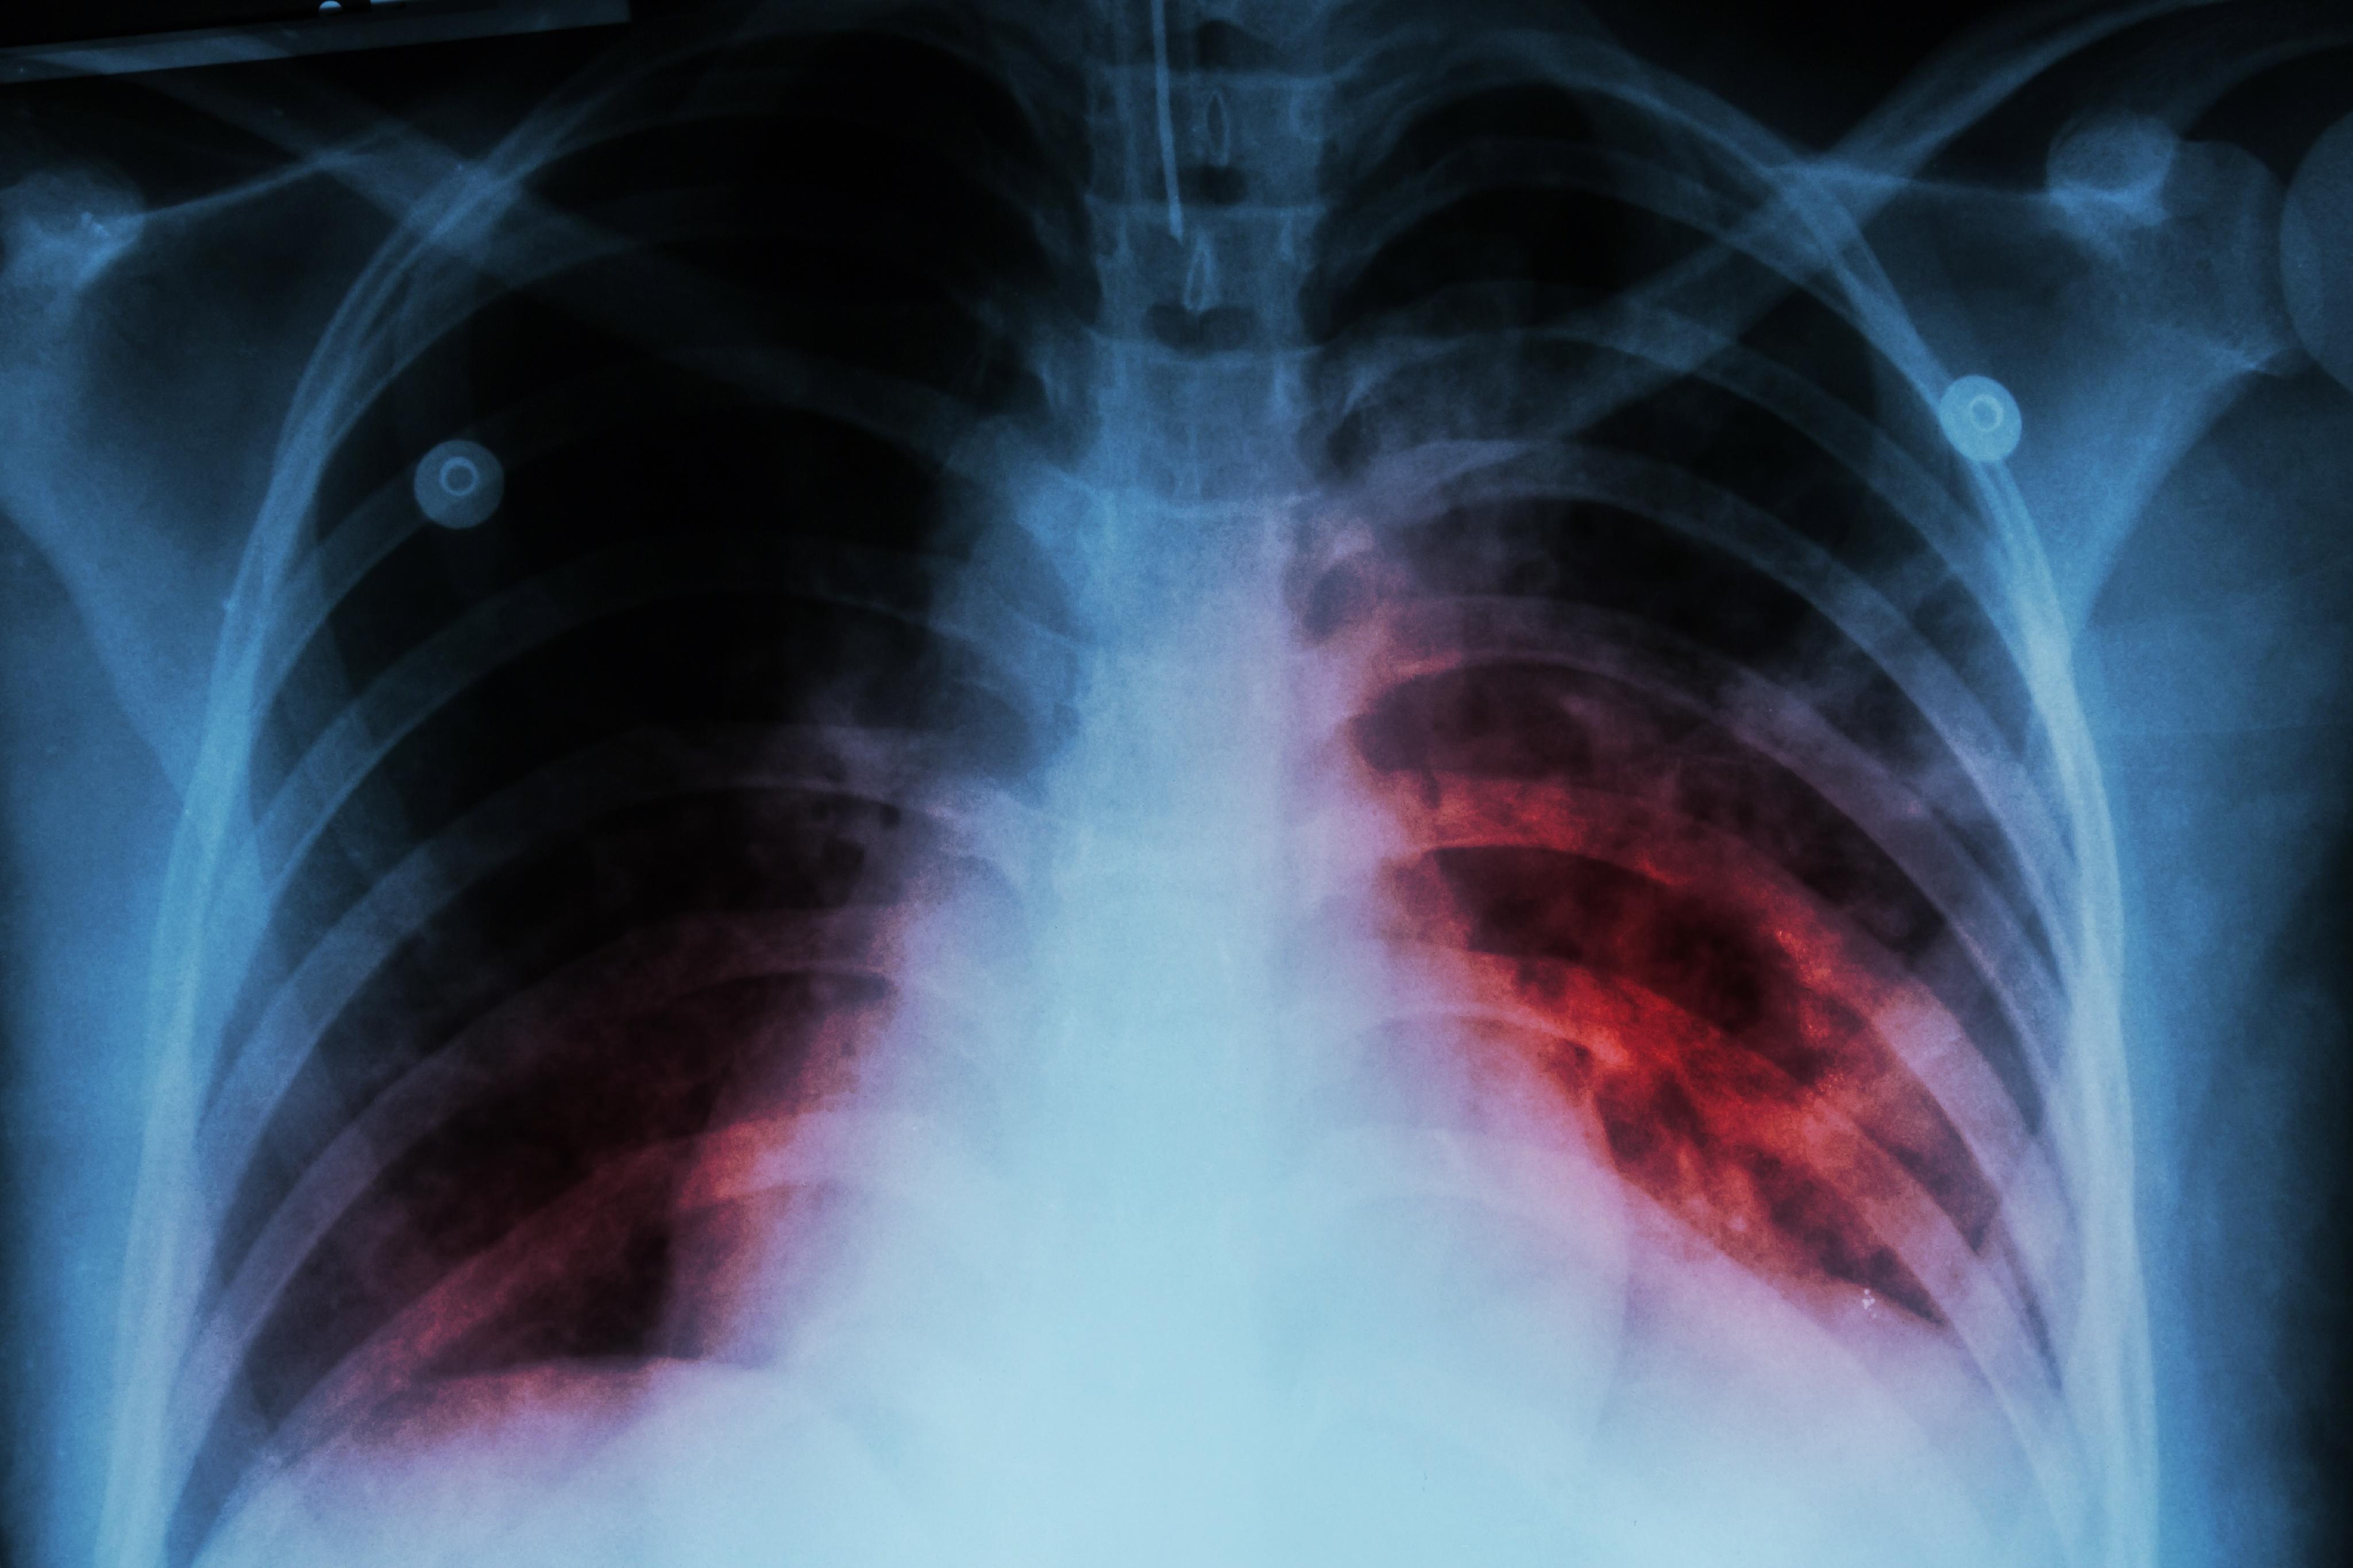

Sonora. — Sonora registra mil 322 casos de tuberculosis respiratoria en este 2025, y Hermosillo concentra más de la mitad, con el 51.2% del total, de acuerdo con el Sistema Único de Información para la Vigilancia Epidemiológica (Suive) de la Secretaría de Salud.

Entre los municipios más afectados del Estado, Hermosillo encabeza la lista con 675 registros, seguido por Cajeme con 118 casos, San Luis Río Colorado (SLRC) con 114, y Huatabampo y Navojoa con 67, según la última actualización de la Semana Epidemiológica 29, que abarca hasta el 19 de julio de 2025.

Ante el caso confirmado de tuberculosis de una estudiante de la Universidad de Sonora, el infectólogo Dr. Alejandro González Mares advirtió que Sonora es el segundo estado a nivel nacional con la tasa más alta de casos de tuberculosis por habitante.